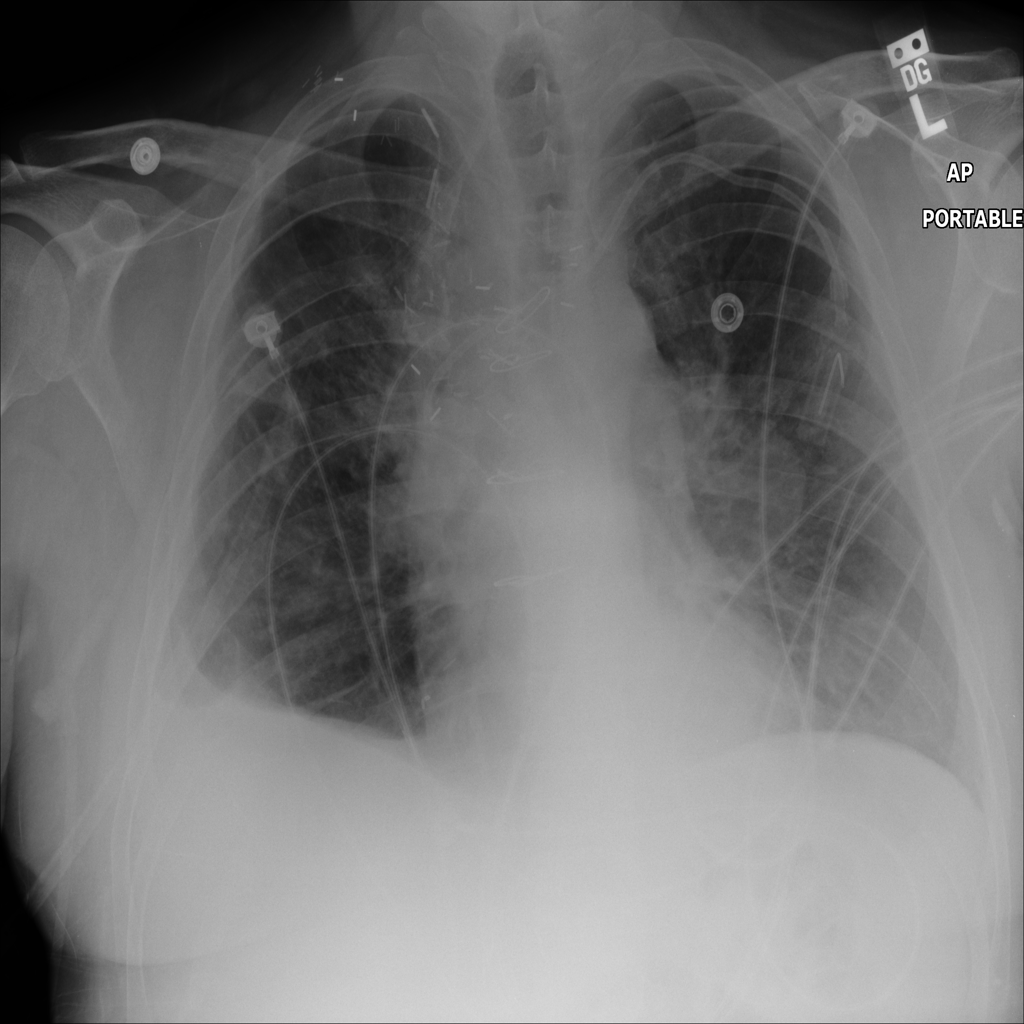

Mass

A mass is a larger focal opacity or lesion seen on the image. It is a descriptive finding that can have several causes and usually needs more imaging or clinical context to characterize.

PAT-C0E5 · IMG-001Mass

PAT-C0E5 · IMG-001

PA